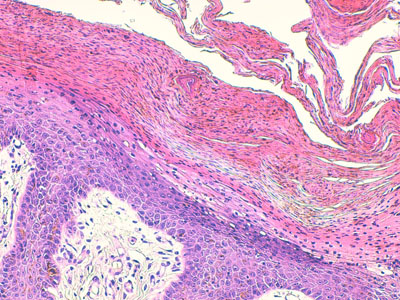

Photo 13 (Hémalun Eosine X 200) : dans certains cas les lésions d’hyperplasie épidermique,

avec émission de crêtes épithéliales ramifiées, prédominent largement le tableau histologique.

Légendes de la Photo 13 :

- Flèche bleue :hyperplasie des couches basales de l’épidermr

- Flèche rouge : parakératose de la couche cornée

- Triangles bleus clairs : contours de crêtes épithéliales allongées, filiformes, ramifiées et branchues, peuplées de cellules basales hyperbasophiles.